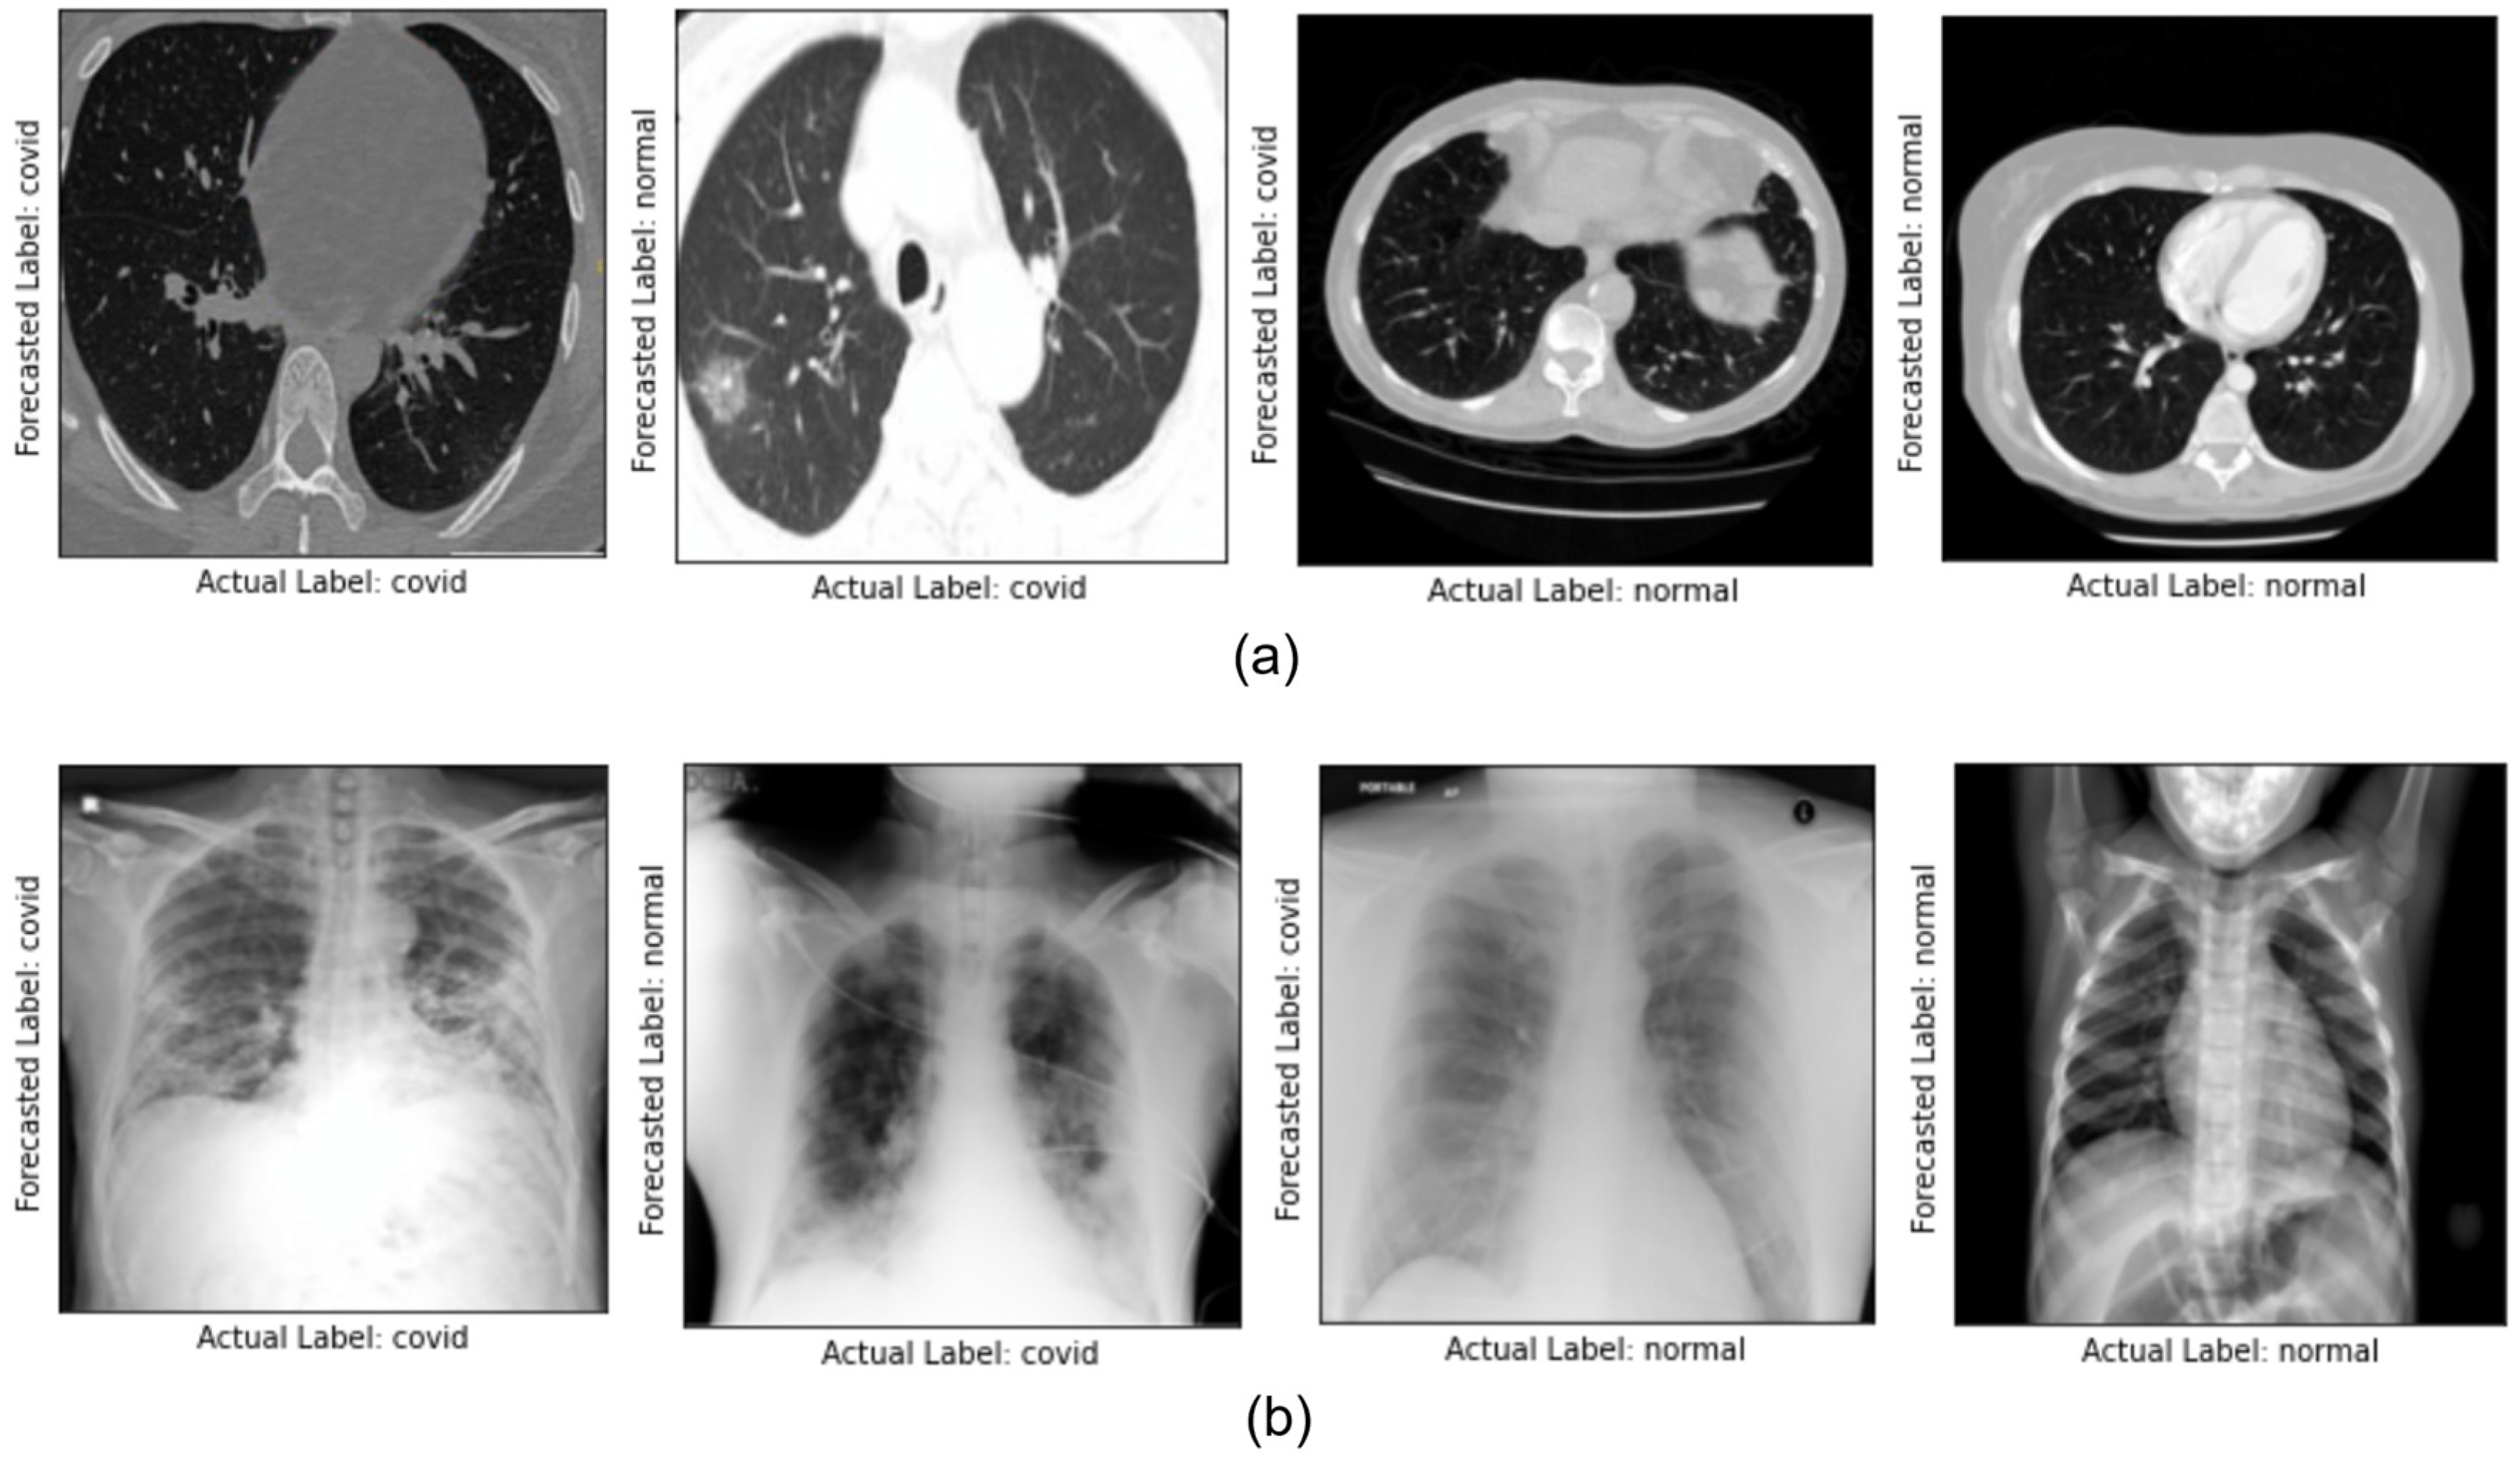

4. Result and Discussion